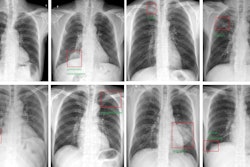

To explore whether an AI model could be a useful screening tool for the condition, the group trained a deep-learning AI model using 207 chest x-rays from 144 patients with esophageal achalasia and 240 chest x-rays from age- and sex-matched individuals without it. The diagnostic capability of the AI model was then verified using a test dataset consisting of 17 chest x-rays from 17 patients with esophageal achalasia and 64 chest x-rays from patients without.